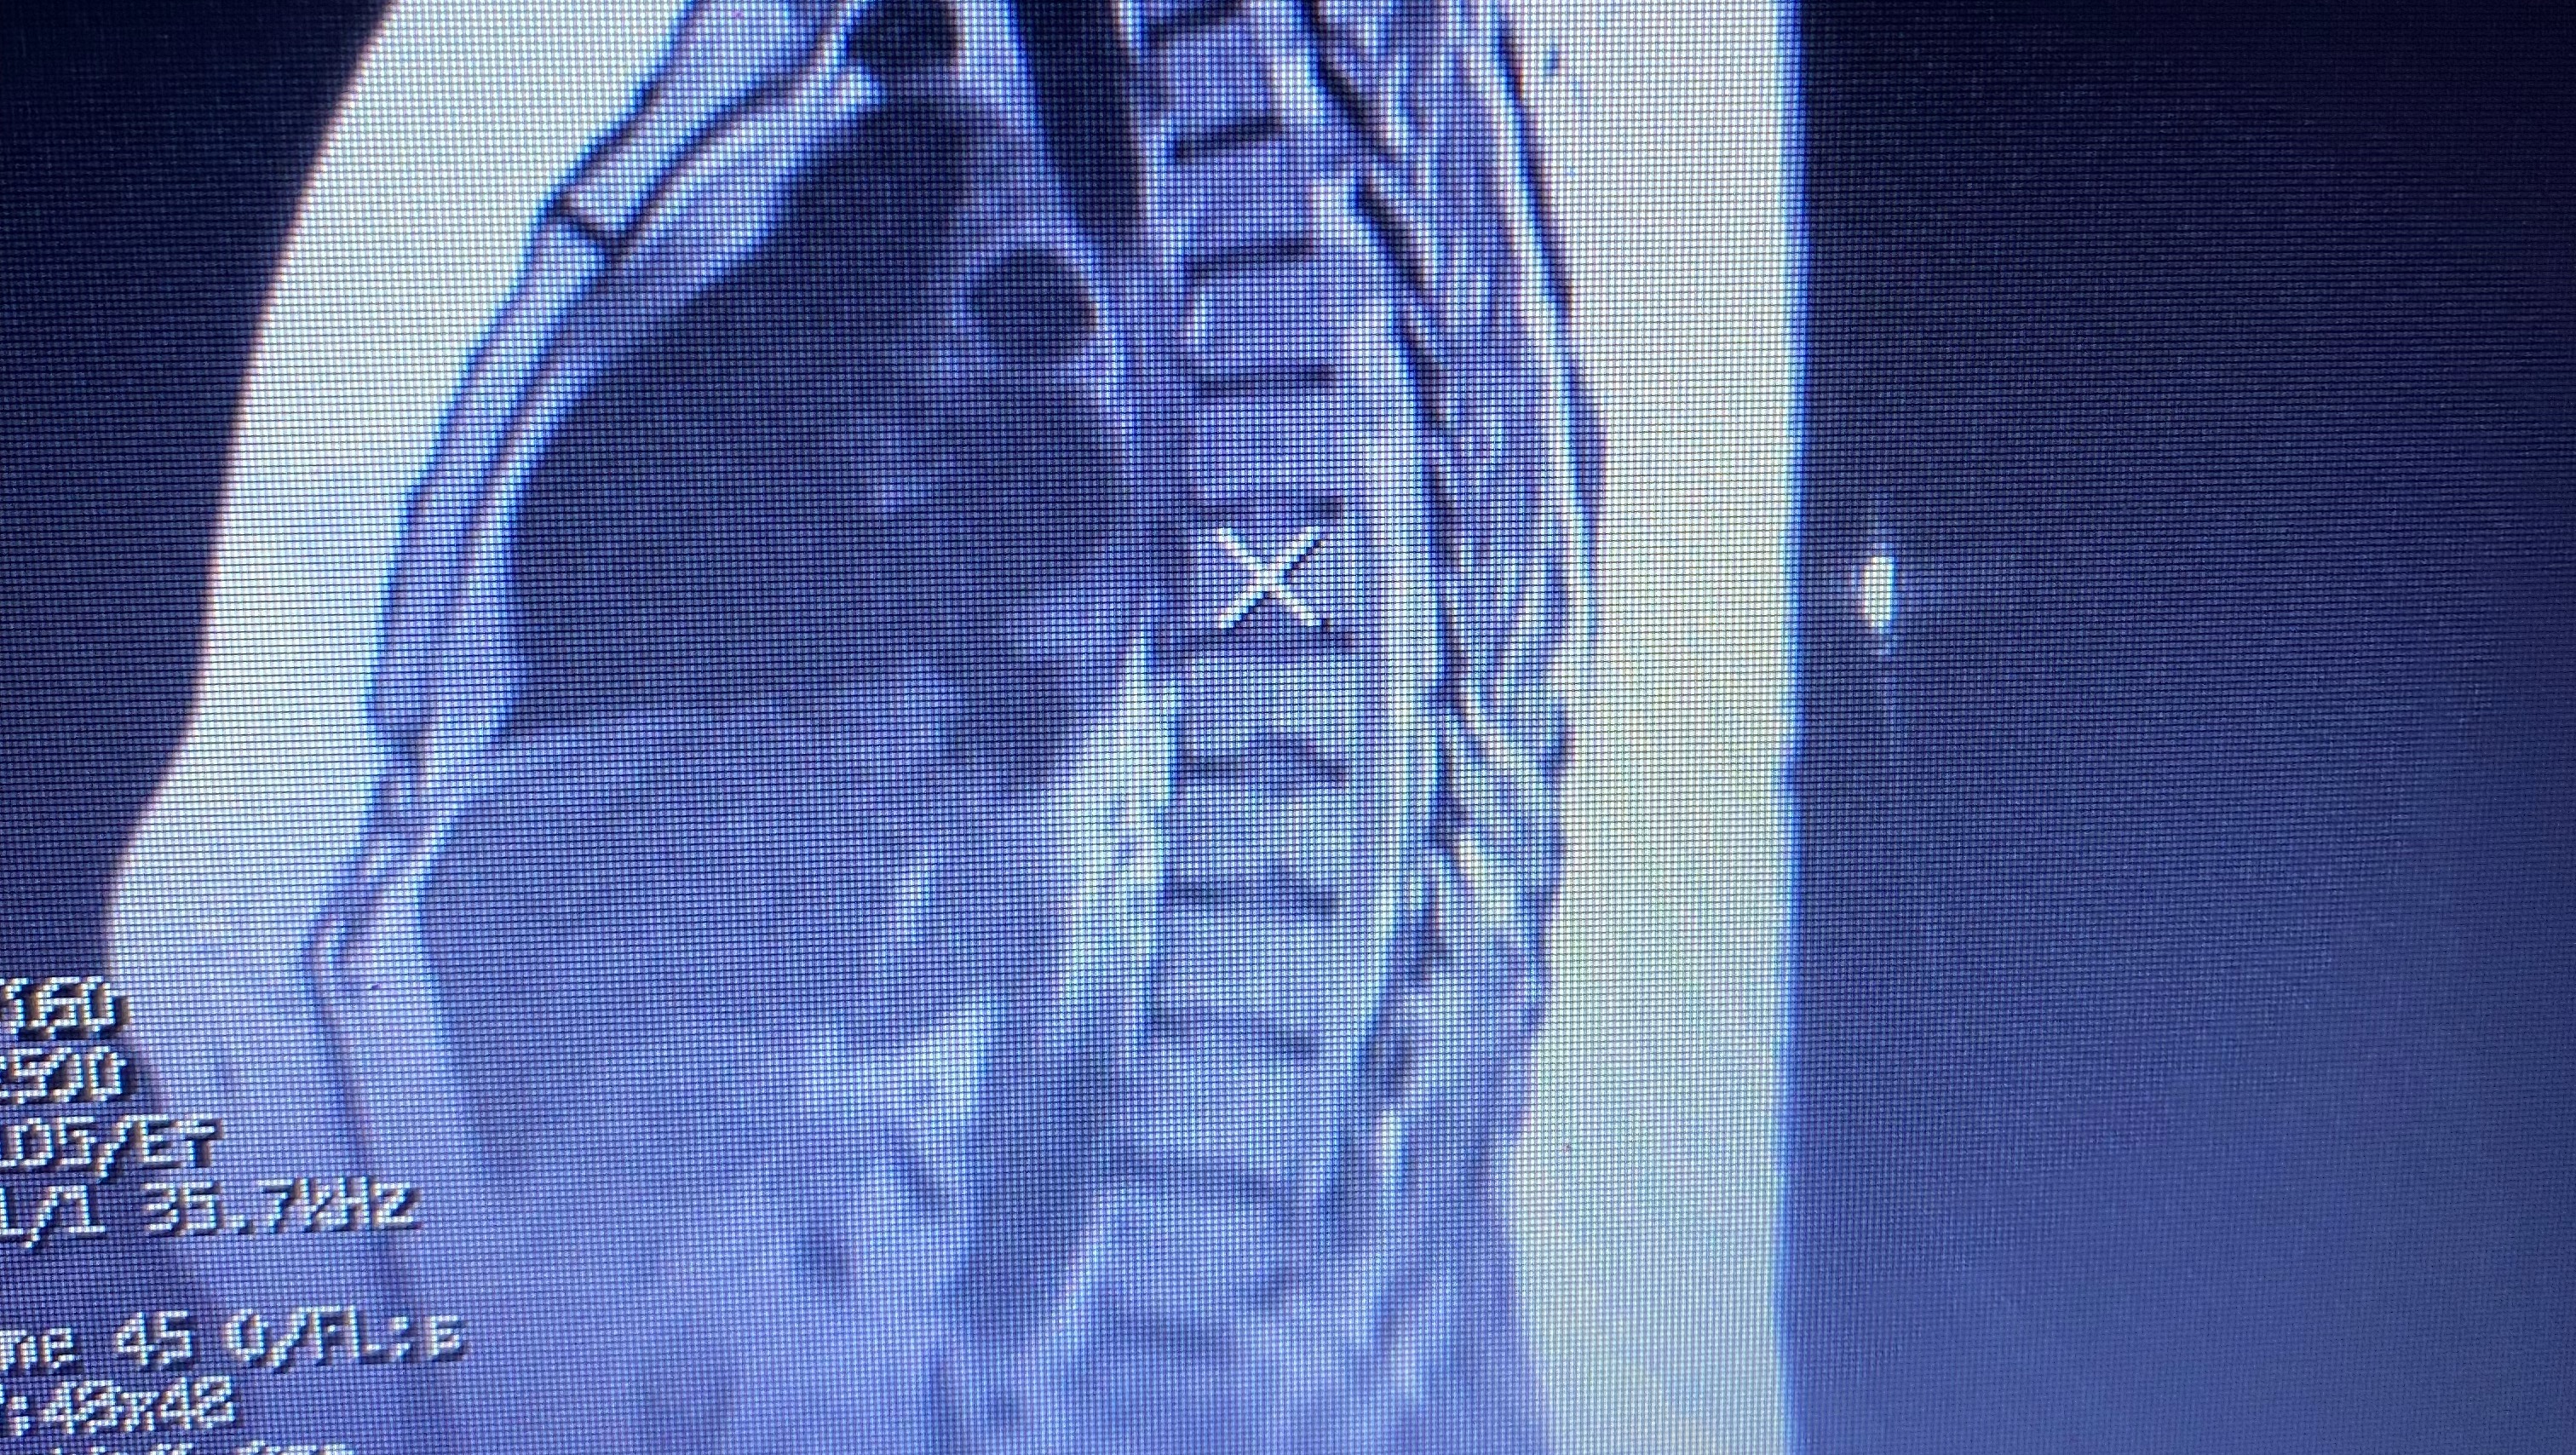

Hello, my name is Cortney. Usually, I’m not one to ask for any type of help. However, due to recent life events, my life has been tossed and thrown upside down. I am usually the one who is always giving help when needed and this time I’m on the other side. It has been 2 weeks since I’ve been able to work and unfortunately I am in the process of being diagnosed with 2 autoimmune diseases. Unfortunately, at this time I do not know when or if I’ll be able to return to work to be able to take care of my son as well as myself, as the doctors and neurologists are still sending me for testing and treatments and infusions. The worry of bills have become a reality.